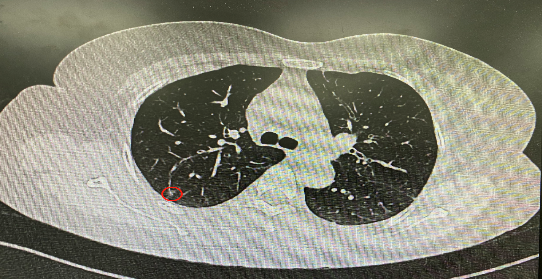

今年54歲的李女士(化名)7月初突然出現(xiàn)右上部腹痛,起初并未在意,以為稍作休息就會(huì)好轉(zhuǎn),但疼痛卻并未消退,持續(xù)了一個(gè)星期。李女士實(shí)在難以忍受,才在家人陪伴下來到西安國(guó)際醫(yī)學(xué)中心醫(yī)院就診。胸外科二病區(qū)崔凱主任接診患者后,詳細(xì)詢問病情并查閱檢查資料,經(jīng)胸部HRCT檢查,結(jié)果提示:右肺上葉后段混合密度結(jié)節(jié)影,考慮原位癌可能,即將患者收入胸腔外科二病區(qū)住院治療。

使用術(shù)前規(guī)劃系統(tǒng)重建全肺3D模型,并于外科醫(yī)生討論染色位置,最終確定標(biāo)記染色點(diǎn)—右肺上葉后段b亞段(RB2b)。術(shù)中使用P290(4.9mm外徑)標(biāo)準(zhǔn)支氣管鏡,根據(jù)導(dǎo)航術(shù)前規(guī)劃路徑,Lung Pro實(shí)時(shí)導(dǎo)航下,GS鞘管進(jìn)入RB2b遠(yuǎn)端官腔外病灶并注射亞甲藍(lán)染色劑。

一切準(zhǔn)備就緒,7月15日,崔凱主任團(tuán)隊(duì)聯(lián)合歐陽(yáng)海峰主任團(tuán)隊(duì)為患者行單孔胸腔鏡下右肺上葉后段切除術(shù),手術(shù)用時(shí)128分鐘順利完成。進(jìn)入胸腔后,亞甲藍(lán)染色部位明顯,患者發(fā)生癌變的右肺上葉后段被成功切除。術(shù)后標(biāo)本根據(jù)染色部位迅速找到結(jié)節(jié),剖開位置兼染色位置和病灶完全符合,行術(shù)中冰凍后快速送病理檢查。經(jīng)術(shù)后病理檢查,明確診斷為(右肺上葉)原位腺癌。